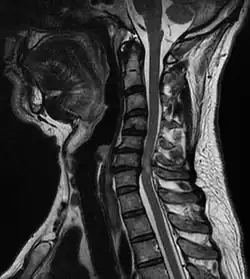

A tumour causing spinal cord compression

Compressive myelopathy at the C6-C7 level due to disc protrussion

Diagnosis is by X-rays but preferably magnetic resonance imaging (MRI) of the whole spine.[3][4]